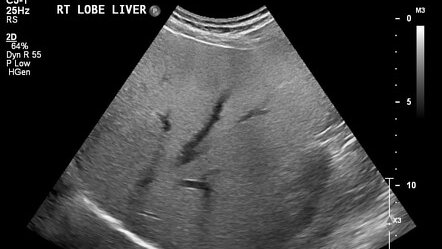

Стеатоз — что это такое

Стеатоз — это накопление жира в тканях. Чаще всего это состояние поражает печень. Накопление жира в печени может привести к заболеваниям печени. Здоровая печень содержит некоторое количество жира, но если жир составляет более 5-10% от веса печени, врачи называют это жировой дистрофией печени, или стеатозом. Чаще всего это состояние наблюдается при неалкогольной жировой болезни печени. Неалкогольная жировая болезнь печени (НАЖБП) включает в себя целый ряд заболеваний печени, которые наблюдаются у людей, употребляющих мало алкоголя или вообще не употребляющих его...